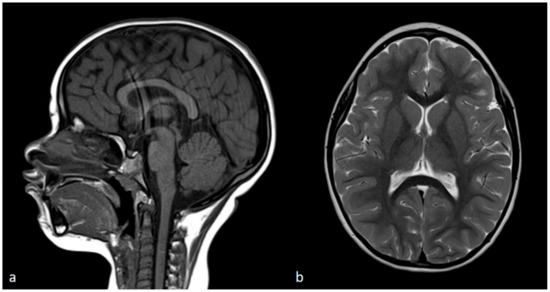

3.1. Clinical Findings